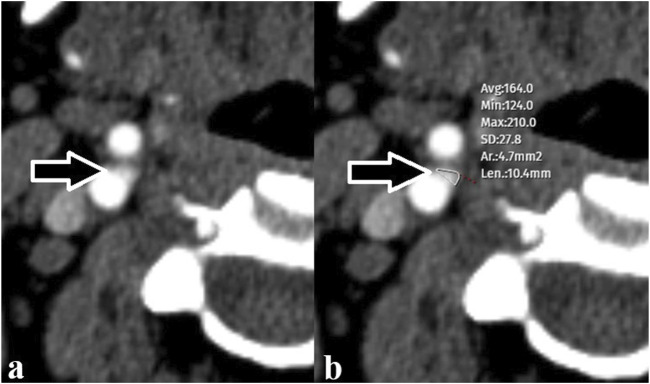

Methods: We retrospectively evaluated patients who were hospitalized for COVID-19 pneumonia during the pandemic in our hospital and who had CTA examinations at least 3 months after treatment. We drew a Region of Interest (ROI) from the periphery of both carotid bodies and measured the area from the widest part. Similarly, measurements were taken in the control group without a history of COVID-19, and the results of the two groups were compared statistically.

Results: We performed measurements on CTA images of 104 control subjects and 108 patients. The total carotid body area of the patients with COVID-19 pneumonia was 4.9 ± 3.7 mm2, and the carotid body area of the control group was 3.7 ± 2.4 mm2. In comparing the two groups, the carotid body area was found to be statistically significantly larger (p < 0.05) in patients with COVID-19 pneumonia.